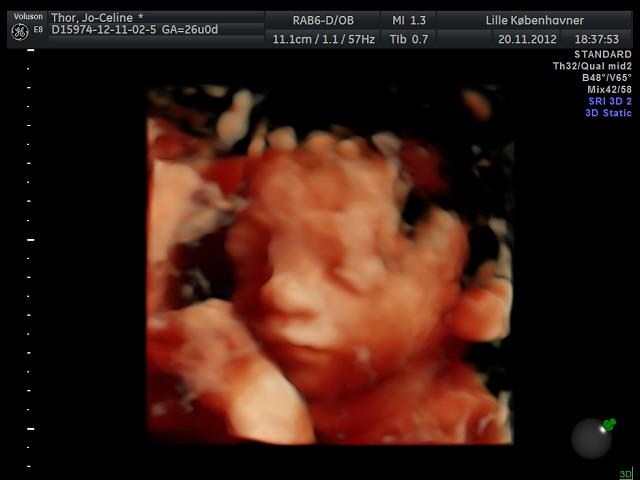

Synes også Lille Kbh'er var dårlige (var afsted før uge 12 i en graviditet sidste år som endte i en MA), og der var kvaliteten rigtig ringe men de har fået uddannede JM ind og fået nyt udstyr så gav dem en chance og kan kun give

for deres service og kvalitet nu. Ihvertfald deres 3D HD.

Du kan lige se et billede af vores pige i 3D 26+0

Vedhæftede fotos (klik for at se i fuld størrelse)